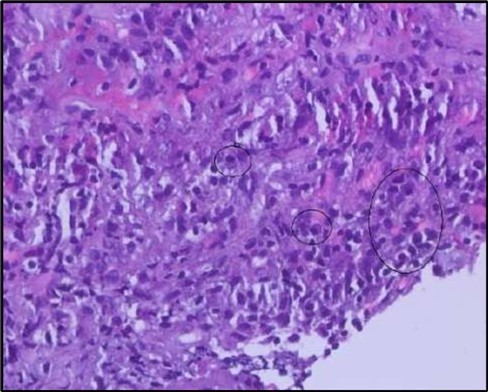

Figure 5b.OS, High-power H&E view showing dense inflammatory infiltration within the corneal stroma composed predominantly of lymphocytes and numerous plasma cells (circles highlight plasma cells).

Histopathological examination revealed a dense infiltration of CD138-positive plasma cells within the excised conjunctival tissue (Figure 5b, Figure 5c, Figure 5d). This finding supports an antibody-mediated immunopathogenesis in Mooren’s ulcer, consistent with Type II and Type III hypersensitivity mechanisms described in the literature 20, 21. The prominent presence of CD138- positive plasma cells provide a clear pathological rationale for conjunctival resection, as excision of the immunologically active perilimbal conjunctiva effectively removes the local 'factory' of autoantibodies that drive corneal stromal destruction, thereby halting ongoing tissue damage 21.